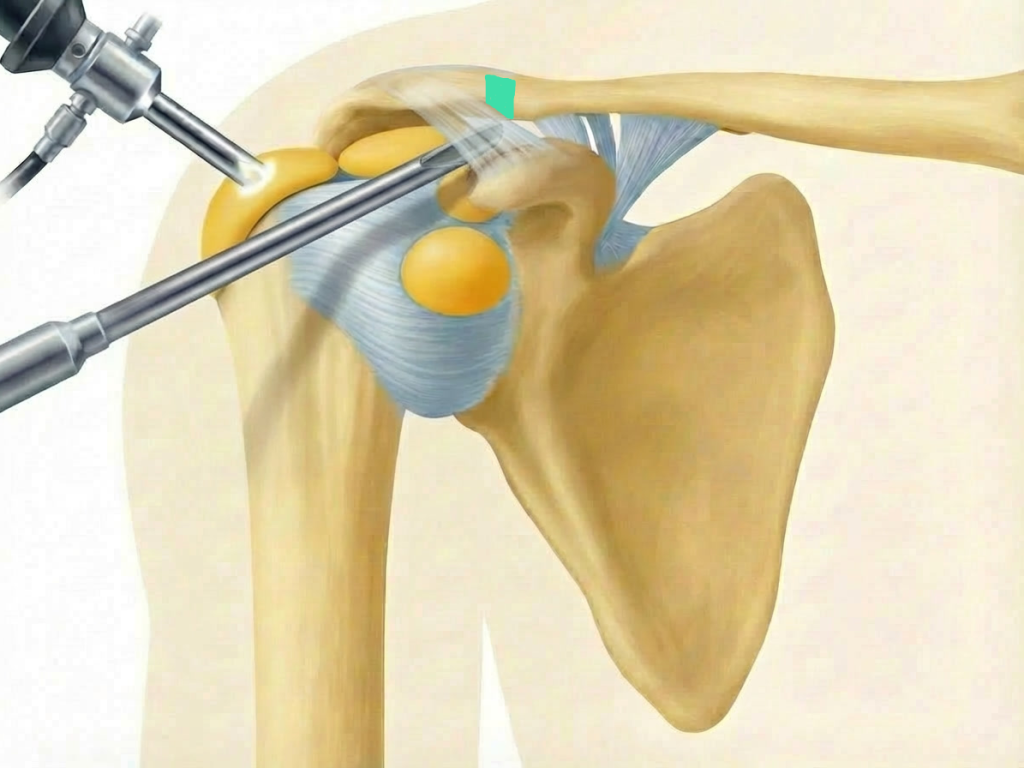

ac gelenkresektion von dr. timmel von ortho-timmel.at

Abtragen der lateralen Clavikula

• Abtragung von ca. 5-10 mm des lateralen Klavikulaendes

• Instrumente:  motorisierte Shaver

• Kontrolle: ausreichender Spalt ohne Knochenkontakt bei Bewegung

subakromiale dekompression von dr. timmel von ortho-timmel.at